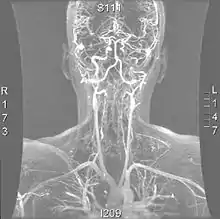

- Черепно-хребцева нестабільність: спричинена травмою ділянок голови і шиї, таких як струс мозку. Зв'язки в шиї нездатні заживати належним чином, тому структура шиї не має здатності підтримувати череп, який потім може потрапити в стовбур мозку, блокуючи нормальний потік спинномозкової рідини, що призводить до проблем, пов'язаних з відмовою вегетативної нервової системи правильно працювати.[37].